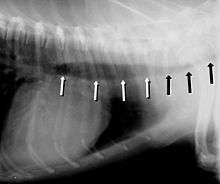

Symptoms include a cough (often called a "goose honk cough" due to its sound), especially when the dog is excited. This cough is usually paroxysmal in nature. Other symptoms include exercise intolerance, respiratory distress, and gagging while eating or drinking. Tracheal collapse is easily seen on a radiograph as a narrowing of the tracheal lumen. Treatment for mild to moderate cases include corticosteroids, bronchodilators, and antitussives. Medical treatment is successful in about 70 percent of tracheal collapse cases.[4] Severe cases can be treated with surgical implantation of a tracheal stent (inside or outside of the trachea) or prosthetic rings. Extraluminal (outside the trachea) stenting is generally only used for tracheal collapse in the neck region. Intraluminal stenting has shown more promise for success with intrathoracic cases, especially using nitinol, a type of shape memory alloy composed of nickel and titanium. Potential problems include stent migration and fracture.[5]